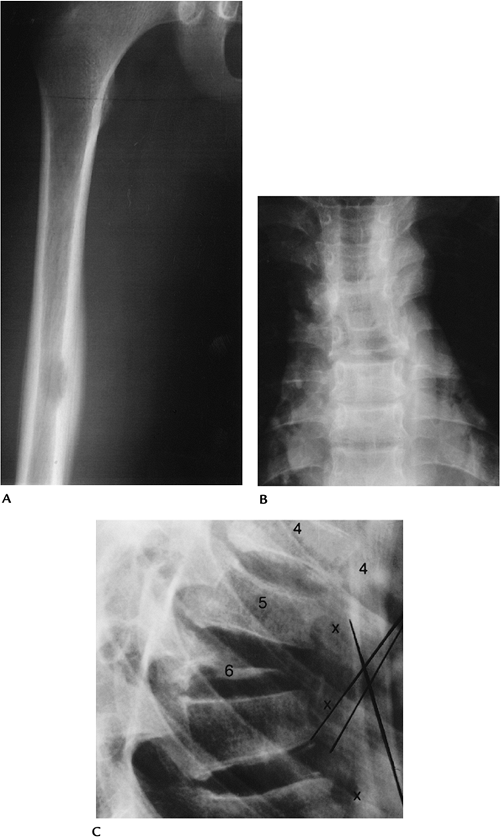

Radiographic features include long bone

sclerosis and prominent trabeculae with sparing of the axial skeleton.

Bilateral symmetric involvement is common. Histologic changes resemble

Hand-Schüller-Christian disease.

FIGURE 12-9 Erdheim-Chester disease. (A) Radionuclide bone scan showing increased tracer in both femora and tibiae. AP (B,C) and lateral (D,E) radiographs of the tibiae showing sclerotic areas with prominent trabeculae.